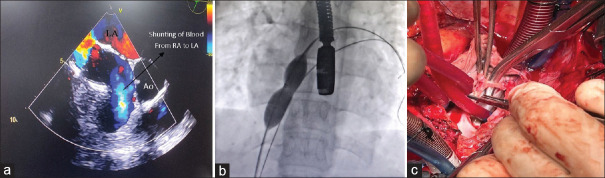

Residual defect after surgical closure of atrial septal defect is extremely uncommon. This communication reports four cases encountered in a tertiary care center during the last three decades. Clinical diagnosis was challenging, and the diverse presentations included acute ischemic stroke, cyanosis, and right ventricular volume overload. The morphology of the residual defects was complex, and multimodality imaging (transesophageal echocardiography, peripheral venous contrast studies, computed tomography, and balloon occlusion) enabled accurate recognition. Percutaneous device closure was feasible in one but required repeat surgery owing to unfavorable anatomy in the others. The communication focuses on difficulties in diagnosis and management.

Abstract Image